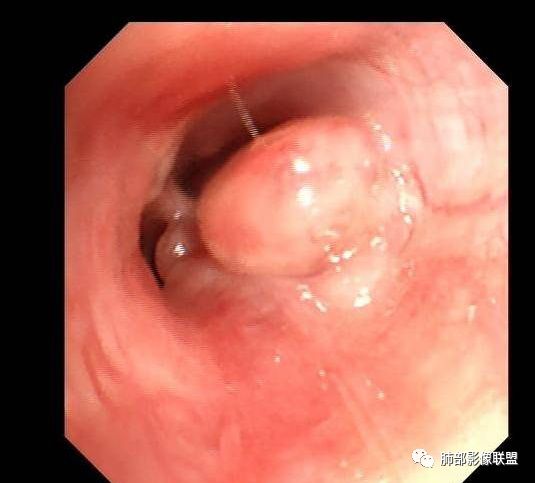

气管镜,右肺中叶见新生物,予活检。

EBUS探及S3、S8站肿大淋巴结,于S8站行TBNA,穿刺抽吸出碎粒样组织送检病理。

经支气管镜淋巴结活检标本:(ES8淋巴结)送检组织示破碎的间质纤维结缔组织内淋巴细胞等炎细胞浸润,其中一小片组织中见多核巨细胞影,未见淋巴组织,请结合临床。

右肺中叶新生物活检:肉芽肿性炎,请结合临床及相关实验室检查除外结核等。

气管镜检查20天后:气管镜灌洗液结核分枝杆菌培养阳性。

最终诊断:肺结核。